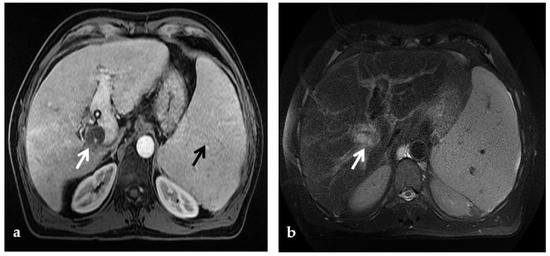

4.2.2. MR

MR is less operator dependent than CDUS, though more so than CT. Similar to CT, MR readily depicts typical findings of PVT including the extent of portal vein occlusion, potential occlusion of the superior mesenteric and splenic veins, and the extent of portosystemic collaterals and secondary changes in the liver (Figure 7). In the evaluation of portal cavernoma cholangiopathy, magnetic resonance cholangiopancreatography (MRCP) better depicts the changes in the biliary system than CT—avoiding ionizing radiation and providing high-quality images of the bile ducts and vessels—and replaces the diagnostic role of percutaneous transhepatic cholangiography and ERCP, reducing the risks of bleeding and acute pancreatitis associated with the latter [49]. One typical finding is the ‘‘wavy’’ appearance of the biliary ducts related to extrinsic compression by the collateral vessels, which was described in 87.5% of patients in one small retrospective study [46,47]. Other typical MR findings of the biliary system include areas of stenosis and dilatation, angulation of the common bile duct at the level of the superior pancreatic head (with an angle of ≤145 degrees considered significant) [61], and wall thickening of the gallbladder and bile ducts. Wall thickening may be related to intramural varices, as previously described, or ischemic fibrosis [46] (Figure 2). Epicholedochal collateral vessels may appear as punctate foci of intramural enhancement within the ducts on postcontrast MR images [61]. Bile duct and gallbladder stones are also well depicted on MRCP images. MR can also show other potential complications, including cholangitis and hepatic abscesses [46].

Figure 7.

MR of a 50-year-old male with chronic portal vein thrombosis and portal hypertension. (a) Axial T1-weighted contrast-enhanced MR image shows low signal intensity within the right branch of the portal vein (arrow). Splenomegaly is a typical hallmark of portal hypertension (black arrow). (b) Axial T2-weighted MR image shows that portal vein thrombosis appears of increased signal intensity (arrow).